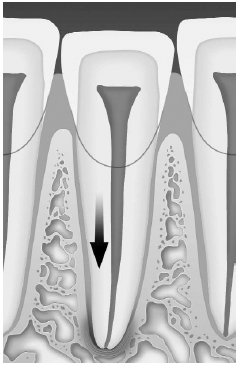

Fractures of the Crown. Crown fractures may be divided into uncomplicated and complicated categories. Uncomplicated crown fractures involve the enamel or enamel and dentin. (See Figure 1.)

Crown fractures through the enamel usually are not sensitive to forced air, hot or cold, or percussion and usually pose no threat to the dental pulp. Immediate treatment in the ED is not necessary but may consist of smoothing the sharp edges off the tooth with an emery board or small hand-held disc sander. It is very important to reassure the patient that a dentist can restore the tooth to its natural appearance using composite resins and bonding materials. Follow-up is important, as pulp necrosis rarely can occur as can color change (0-3%).2,18 (See Figures 1 and 2.)

Fractures that extend into the pulp of the tooth are true dental emergencies. (See Figures 1,4) Fractures through the pulp result in pulp necrosis in at least 10-30% of cases even with appropriate initial dental treatment.2 They are distinguished from fractures of the dentin by the pinkish-red color of the pulp. The fracture surface of the tooth should be wiped off with gauze and observed for frank bleeding or a pink blush, which indicates exposure of the pulp. Pulp fractures usually are severely painful, but occasionally there is a lack of sensitivity secondary to a disruption of the neurovascular supply of the tooth.3